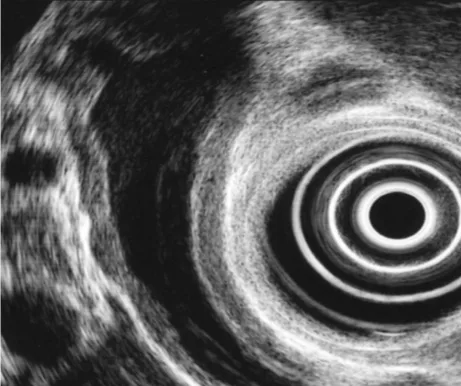

Figure 12. Aspect échoendoscopique de la PAI de type I. Noter l’épaississement hyperéchogène concentrique du CPP au centre de l’hypertrophie hétérogène de la glande